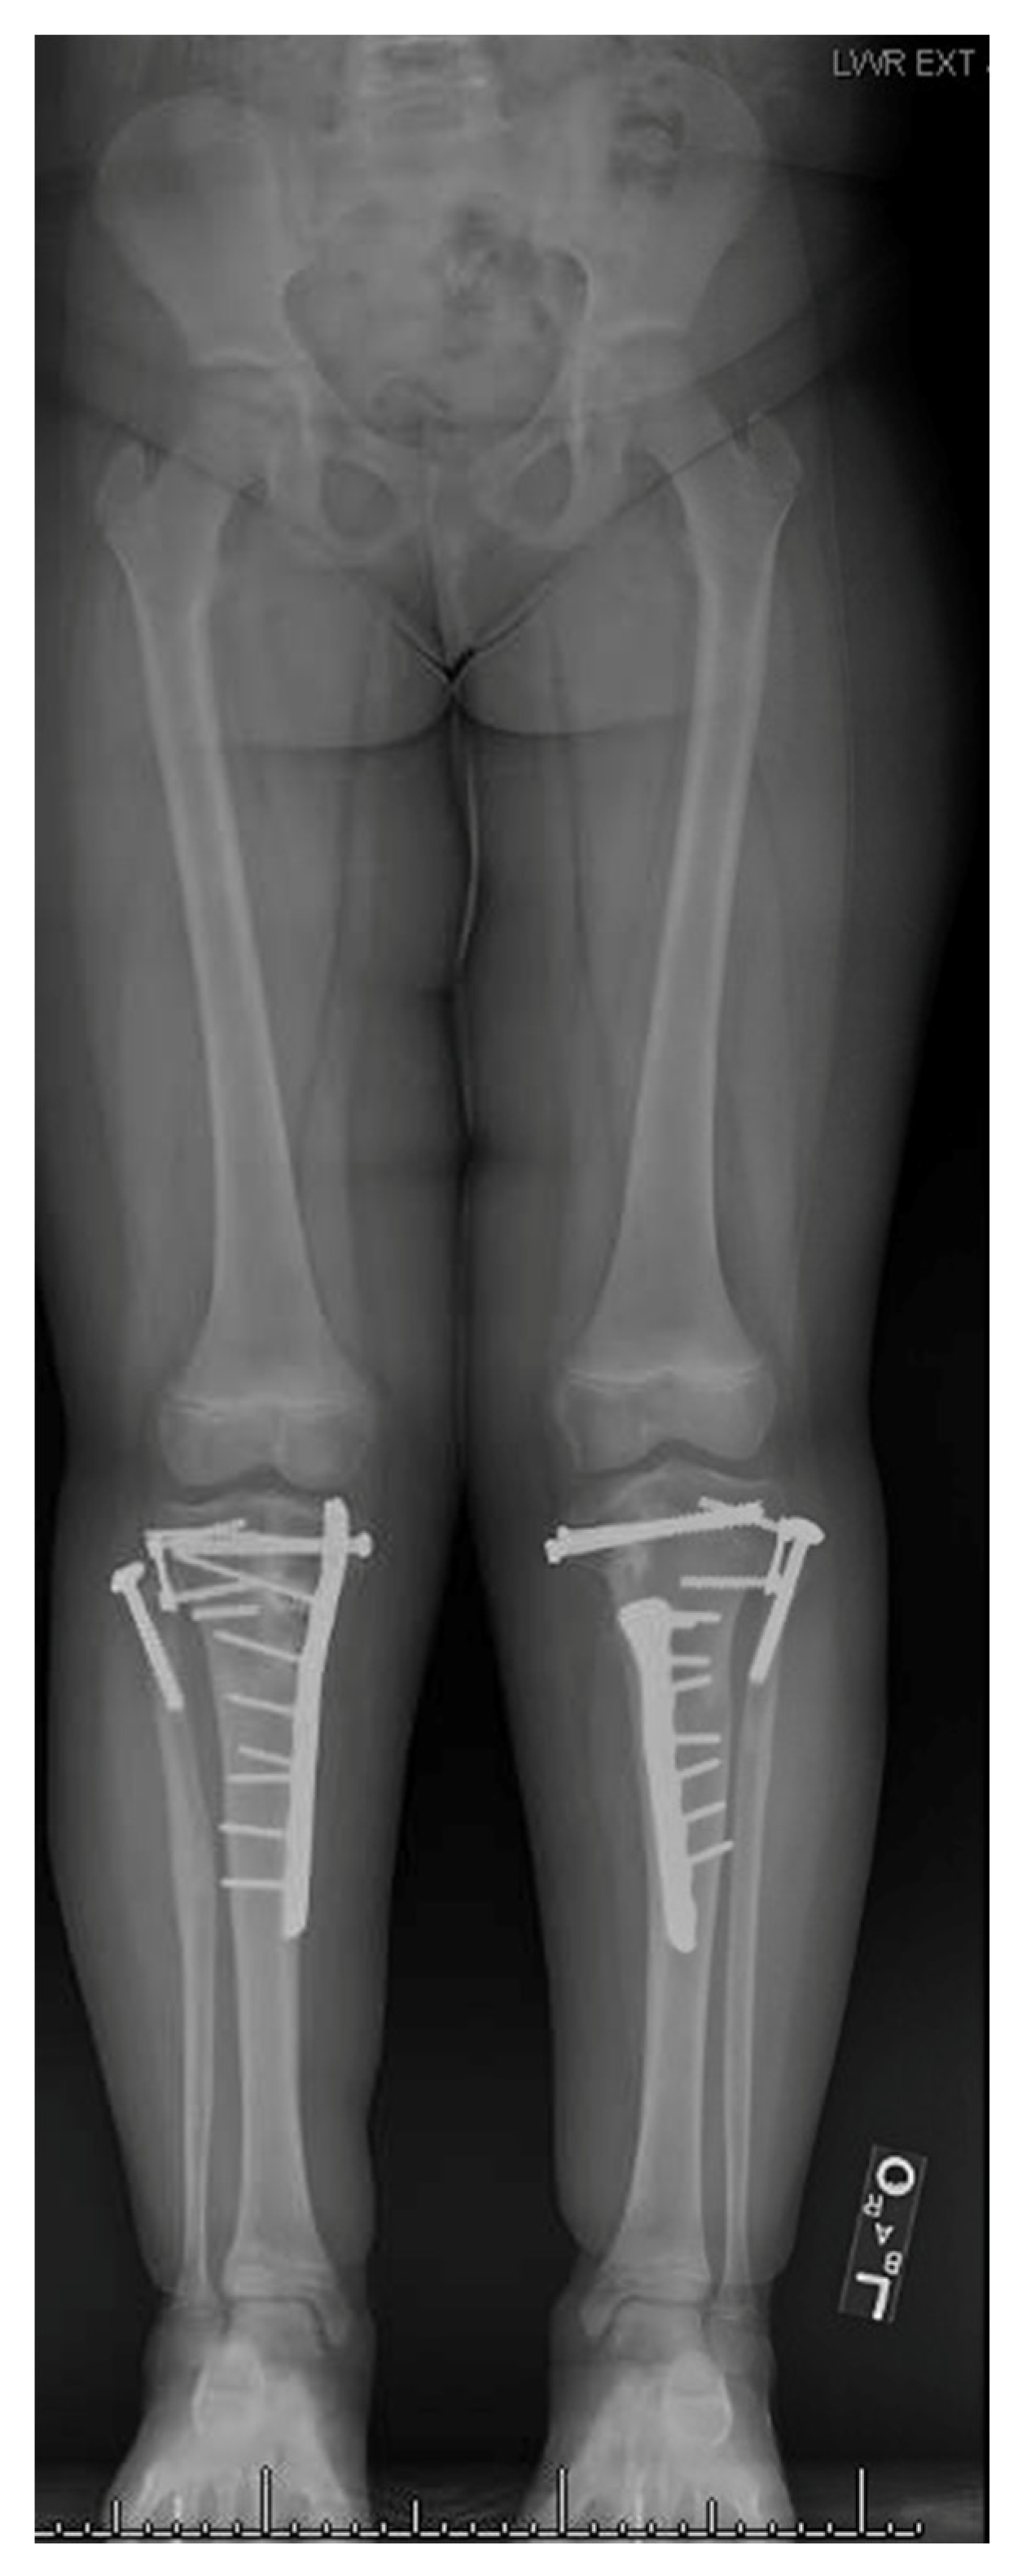

17. Gradual Correction with External Fixation